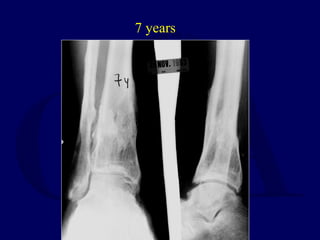

1986 - 24 yo Male

7 years

14 years

 Works light labor

 Prefers high top boots

 Occasional pain

 Ankle score 80